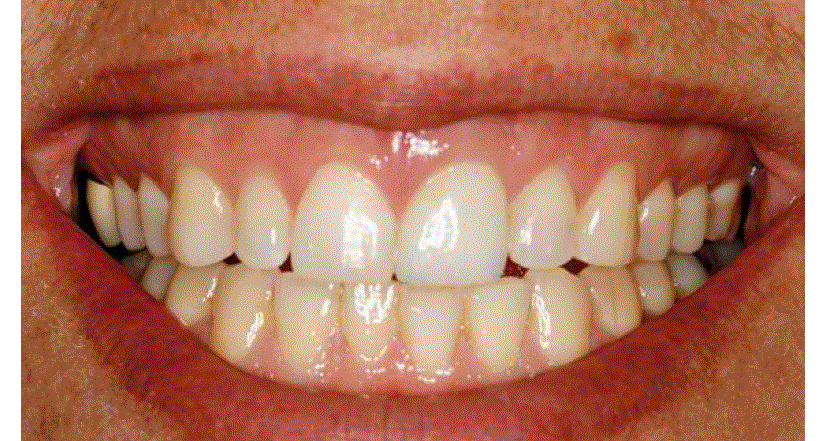

Cet article expose un cas dans lequel une incisive centrale est extraite et un implant placé extemporanément, avec pose d'une couronne provisoire. Le patient présentait une ligne du sourire haute qui montrait toute la denture lors du sourire, créant ainsi le défi.

La couronne provisoire a été mise en sous-occlusion et les contacts inter-proximaux ont été légèrement ouverts. La couronne a été soigneusement polie de façon qu'aucune irritation des tissus ne se produise (figure 2). Cette photo a été prise immédiatement après la chirurgie et le placement de la provisoire.

La figure 4 montre la restauration terminée, après scellement. Une observation attentive révèle une papille intacte, une anatomie correcte des contours de l'épaulement, un tissu gingival ferme et sain, une forme une teinte excellentes et une glazure de l'émail qui se marie avec la denture naturelle.